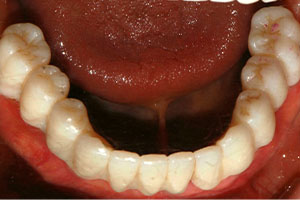

치료증례 전후사진

Before & After